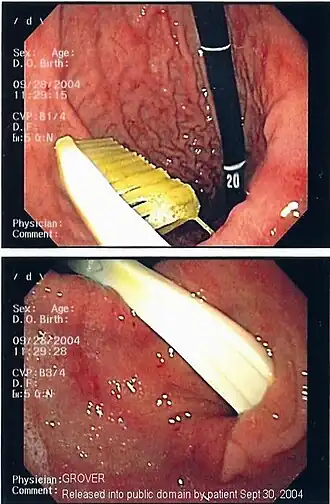

| An endoscopy image of the stomach, showing a foreign body in the form of a swallowed toothbrush. | |